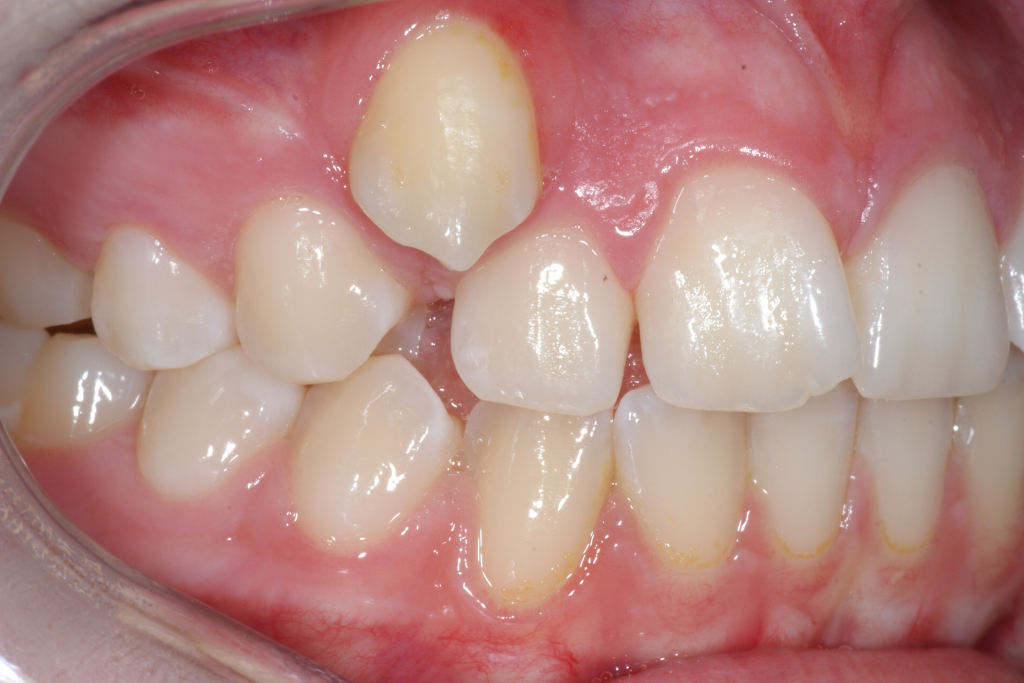

Correction d’une malocclusion de type Classe II subdivision avec canine ectopique (#14).  Des appareils fixes (boîtiers) et l’extraction d’une prémolaire (#15) furent nécessaires pour améliorer ce sourire.  Traitement chez une adolescente, réalisé en 21 mois.